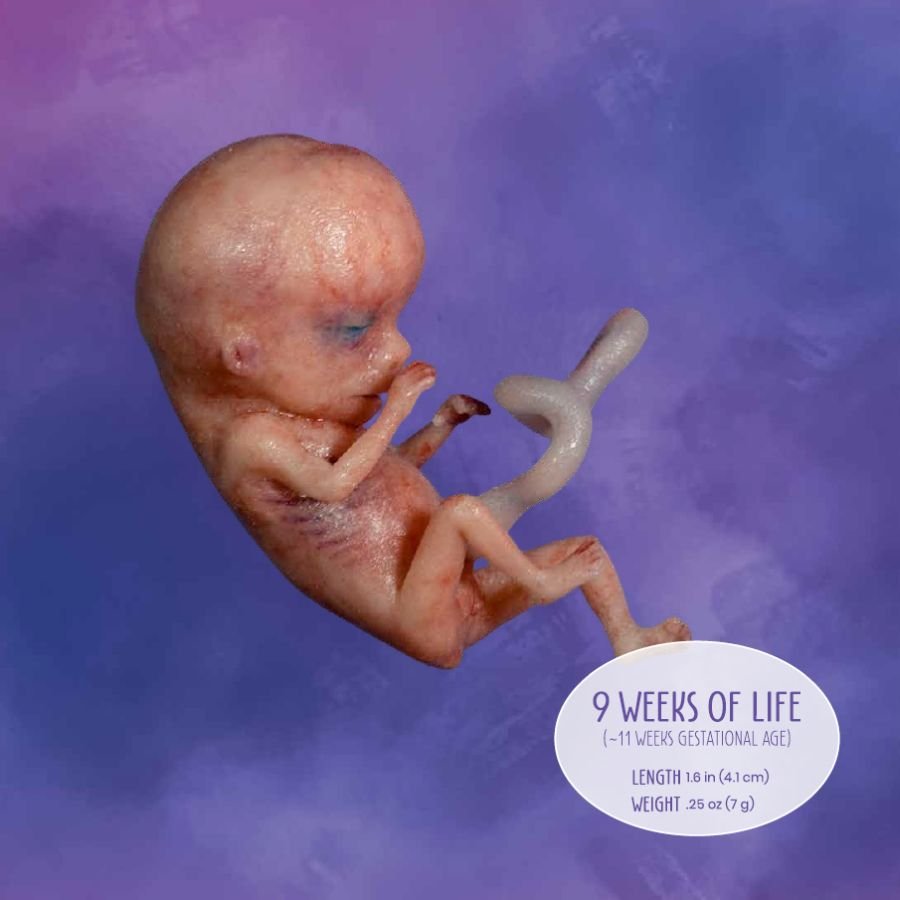

Looking for captivating what does a 2 month old fetus look like images? All, in collaboration with felix.edu.vn, presents a curated selection. Dive into the details for more.

what does a 2 month old fetus look like

Posts: what does a 2 month old fetus look like